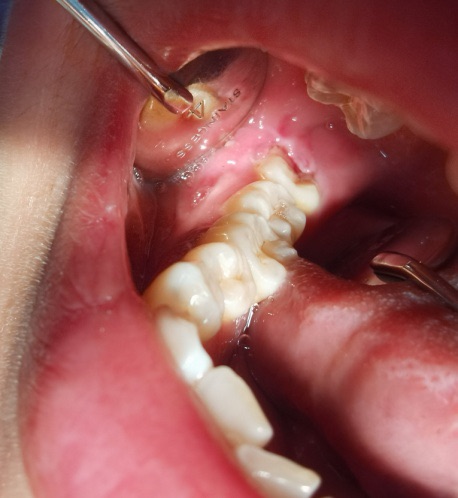

(作者供图 牙体硬组织疾病)

·牙体硬组织疾病 孕期更容易发生龋病,这是因为妊娠期妇女进食频率增加,口腔卫生不易清洁,且口味会发生变化,喜食酸甜的食物,加上女性激素水平变化出现孕吐反应,口腔处于酸性环境,细菌分解蔗糖产生酸性物质,使得牙釉质脱矿,形成龋齿。浅龋一般无自觉症状,中龋多变现为冷、热、酸、甜刺激性疼痛和食物嵌入后疼痛,深龋症状较中龋重,当刺激源去除后疼痛立即消失,无自发性痛。牙体硬组织非龋性疾病主要有楔状缺损、牙磨损和牙隐裂,楔状缺损是牙颈部硬组织发生缓慢消耗所致的缺损,多是因刷牙方式不对导致,症状与中龋相似;牙磨损多是因咀嚼硬物导致的牙体硬组织慢性磨耗;牙隐裂指牙冠表面的非生理性细小裂纹,常不易被发现,表现为冷热刺激敏感或咬合不适。龋病和非龋性疾病若不控制,可近一步发展成牙髓炎和根尖周炎,会给妊娠期妇女带来难以忍受的痛苦。牙髓炎即俗话说的“牙神经发炎”,孕期常见的牙髓炎多为慢性牙髓炎急性发作,表现为自发性阵发性痛,夜间痛,温度刺激加剧疼痛和疼痛不能自行定位,这就是俗话说的“牙痛不是病,痛起来要了命”。根尖周炎多为牙髓炎的继发病,多为死髓牙,指发生于根尖周组织的炎症性疾病,主要表现为牙齿咬合痛,牙龈肿胀、溢脓、长疱(即瘘管),死髓牙若发展为残冠,残根,则需要拔除可能。因此,发现早期牙体硬组织疾病,一定要及时处理,越拖越麻烦,切记小洞不补,大洞吃苦。